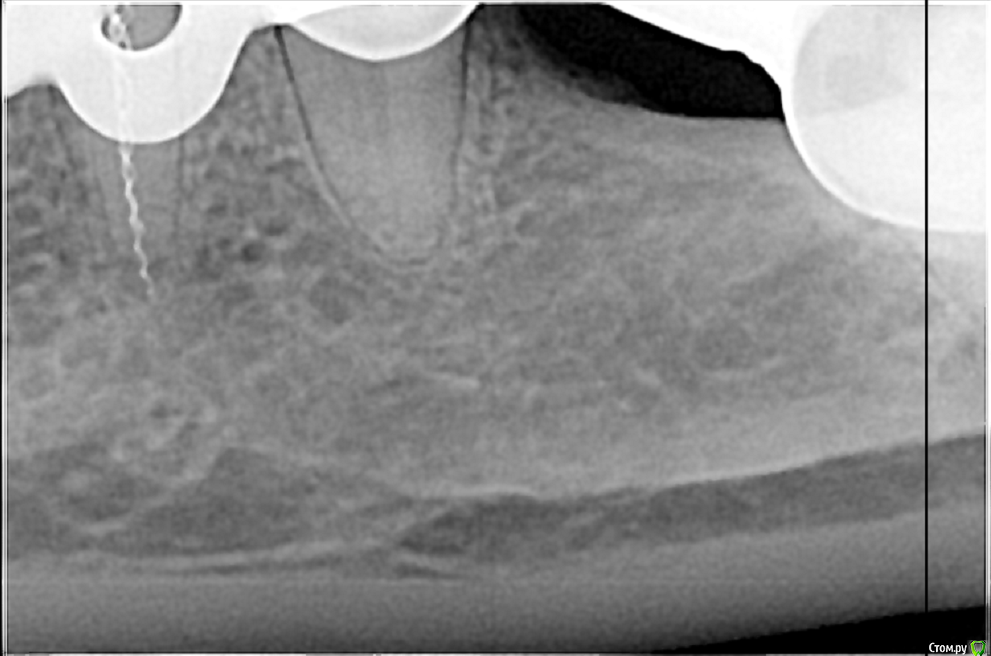

Всем доброго дня! В коем то веке появилась свободная минутка и решил поделиться с вами несколькими кейсами. Обострение хронического периодонтита 27, каналонаполнитель в нёбном канале. Коффердам, извлечение каналонаполнителя, хлорка, лимонка, УЗ, кальций. Обтурация Ah+ латеральная компакция.